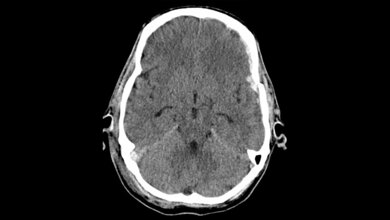

Das Schädel-Hirn-Trauma (SHT) ist ein Krankheitsbild der traumatischen Erkrankungen. Jedes Jahr werden in Deutschland circa 300.000 Patientinnen und Patienten mit einem SHT stationär aufgenommen [12]. Es entsteht durch eine Gewalteinwirkung auf den Kopf des Betroffenen. Dies geschieht häufig durch Stürze oder im Rahmen von Verkehrsunfällen [7]. In diesem Artikel erhalten Sie einen Überblick über das Krankheitsbild SHT und erfahren Informationen zur Epidemiologie, zu den Symptomen, zur Diagnostik, zur Therapie und zur Prognose nach einem SHT.

Traumatic brain injury (TBI) is a clinical picture of traumatic diseases. Every year around 300,000 patients with TBI are hospitalized in Germany [12]. It is caused by a violent impact on the patient‘s head. This often happens as a result of falls or traffic accidents [7]. This article gives you an overview of the clinical picture of TBI and provides information on the epidemiology, symptoms, diagnosis, therapy and prognosis after TBI.